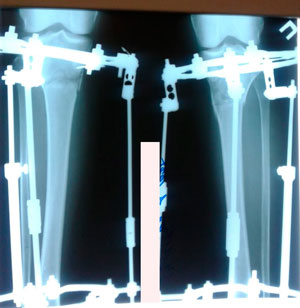

Пациентка - 37 лет.

Диагноз: варусная деформация голеней. Ротация с обеих сторон.

Дата операции - 24.10.2019г.